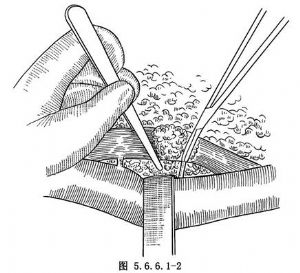

(1)探查肿瘤:开胸后将肺牵向前方,在胸主动脉和下肺韧带之间切开纵隔胸膜(图5.6.6.1-1)并向上下伸延。纵隔疏松的结缔组织中稍大一些的血管须予以结扎,细小者可不处理(图5.6.6.1-2)。如肿瘤在下胸段,可借助下段食管腔内的胃管在纵隔内摸到食管,紧贴管壁以手指作钝性分离,绕过一条纱带将食管提出纵隔,沿食管外壁纵轴方向继续作钝性分离。如此时发现肿瘤与主动脉或左支气管之间有紧密粘连不能分开,则肿瘤不能切除。有时肿瘤虽已侵出食管肌层以外,但与主动脉或左支气管之间尚有间隙可寻,可用手指置于粘连的深部用剪刀紧贴肿瘤将粘连剪开。肿瘤如已累及右侧胸膜,可连同对侧胸膜一并离断。如果瘤体较大术野暴露欠佳,可在肿瘤上方由正常食管处再绕过一条纱带,同时牵引肿瘤上下的两条纱带,瘤体内侧即可获得良好的暴露。将肿瘤与周围组织分开以后继续向上游离食管,预计在肿瘤上缘以上4~5cm处横断食管,由此平面再向上游离4~5cm以便作吻合。注意此部分不宜游离过远,否则将影响食管远端的血运,直接影响吻合口的愈合。